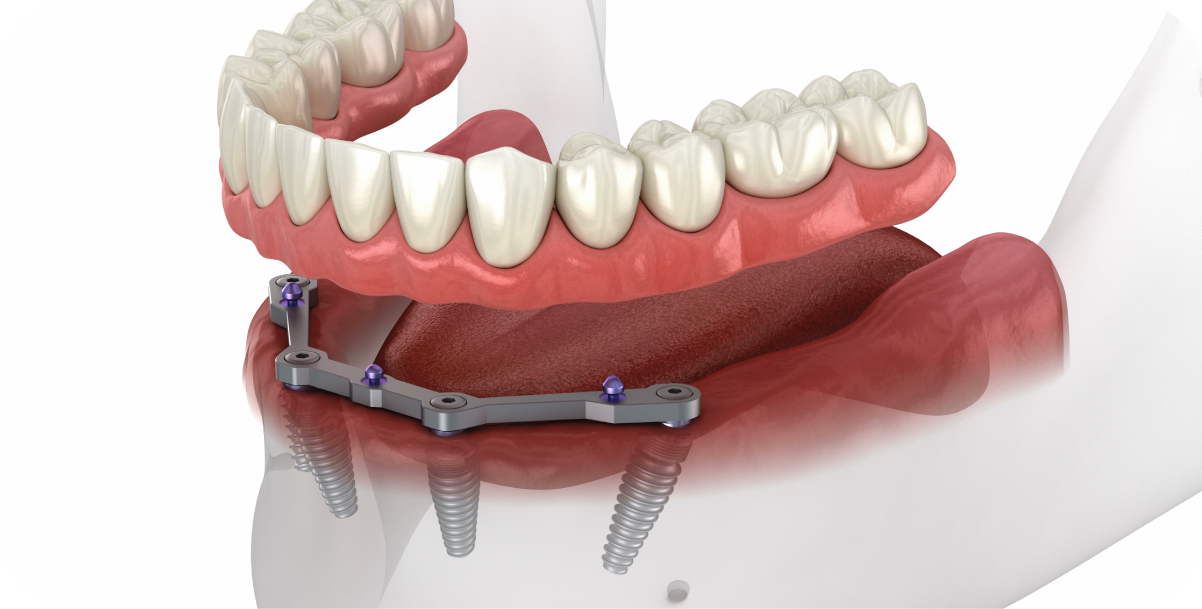

On the other hand, traditional implants are the powerhouses of dental restoration. They’re made up of two parts: a sturdy titanium post that acts like your tooth’s root and an abutment that connects it to a custom crown. This two-piece setup closely mimics the structure of a natural tooth, so much so that you might forget it’s not the real deal.

Traditional implants are incredibly versatile, making them perfect for single teeth, multiple gaps, or even full-arch solutions like the All-on-4 system. If you’re after strength and longevity, these implants are thought of as the gold standard.

Whether you’re missing a single tooth or a whole arch, traditional implants have your back. Options like the All-on-6 system can give you a fully functional, brand-new smile.